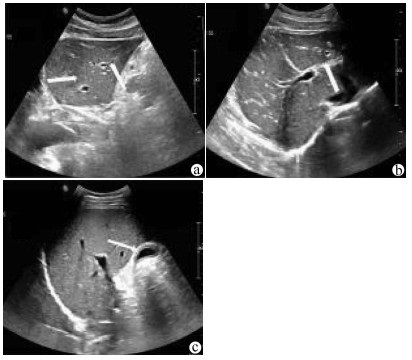

Influence of arterial variation and reconstruction of the donor hepatic artery in liver transplantation on early postoperative arterial complications

2021, 37(8): 1901-1904. DOI: 10.3969/j.issn.1001-5256.2021.08.030

Abstract(1199) HTML (300) PDF (2761KB)(185)

Abstract: